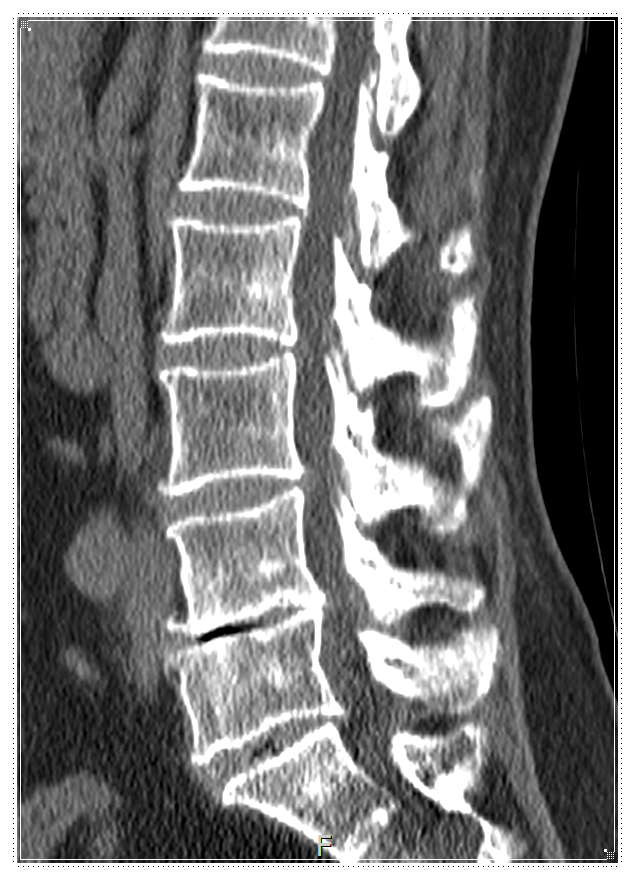

골반이 조금씩 틀어지고,

그 위에 척추가 비뚤어진 상태가

오랜 시간 유지되면서

문제가 시작되는 경우가 많습니다.

이 과정에서

주변 근육은 계속 긴장하게 되고,

디스크에는 한쪽으로 압력이 쏠리게 됩니다.

✔️ 골반이 어떤 상태로 서 있는지

✔️ 척추가 어떤 방향으로 쌓여 있는지

✔️ 걷거나 앉을 때 몸이 어떻게 버티는지

디스크의 상태, 신경 압박 여부,

근육 긴장도를 종합해

치료 방향을 설정합니다.